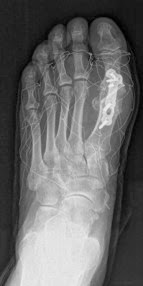

En este nuevo post os quería mostrar otro caso de Hallux Rigidus que se me ha presentado y que he operado con éxito. Lleva 1 mes de evolución y de momento no hay complicaciones. Se trata de un paciente anciano y dado el grado de artrosis y su edad lo indicado es la artrodesis (fusión de la articulación) y es lo que realicé.

Actualmente está si dolor apenas aunque todavía es pronto para darle el alta definitiva. La ventaja de este material es que al llevar tornillos bloqueados a la placa dan mucha mayor estabilidad y se le puede permitir al paciente el apoyo del pie desde el principio, siendo la recuperación mucho más rápida por tanto. La he remitido a Rehabilitación para ganar movilidad y queda por tanto pendiente de nueva revisión con Radiografías de control. Estas son las Radiografías antes y después de la cirugía: |